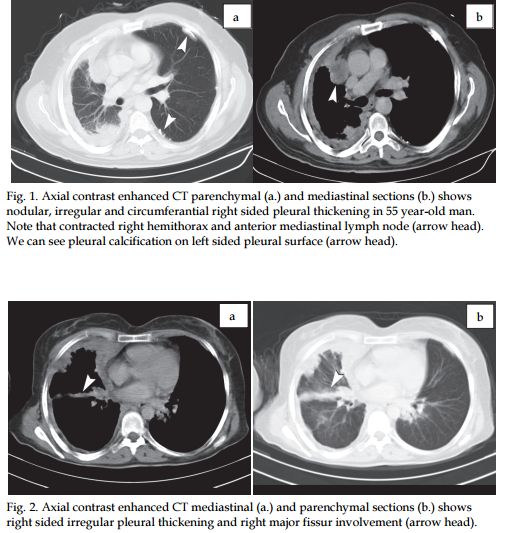

Radiological Findings In A Case Of Advance Staged Mesothelioma Aziz Journal Of Thoracic Disease Localized Malignant Mesothelioma